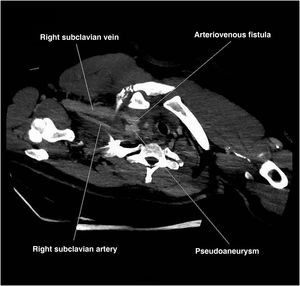

Patient with a firearm injury to the right side of his neck. When treated by the medical services, the patient was found to be conscious, breathing normally, and hemodynamically stable. Airway isolation was performed, followed by a cervico-thoracic coronary computed tomography angiography (CCTA), which revealed both in the axial-oblique view (Fig. 1) and from the posterior view of a 3D reconstruction (Fig. 2), a laceration of the proximal third of the right subclavian artery, resulting in a pseudoaneurysm, and of the right internal jugular vein, leading to an arteriovenous fistula, which explained the patient's maintained hemodynamic stability and a hemoglobin level of 12.1g/dL until surgical repair.